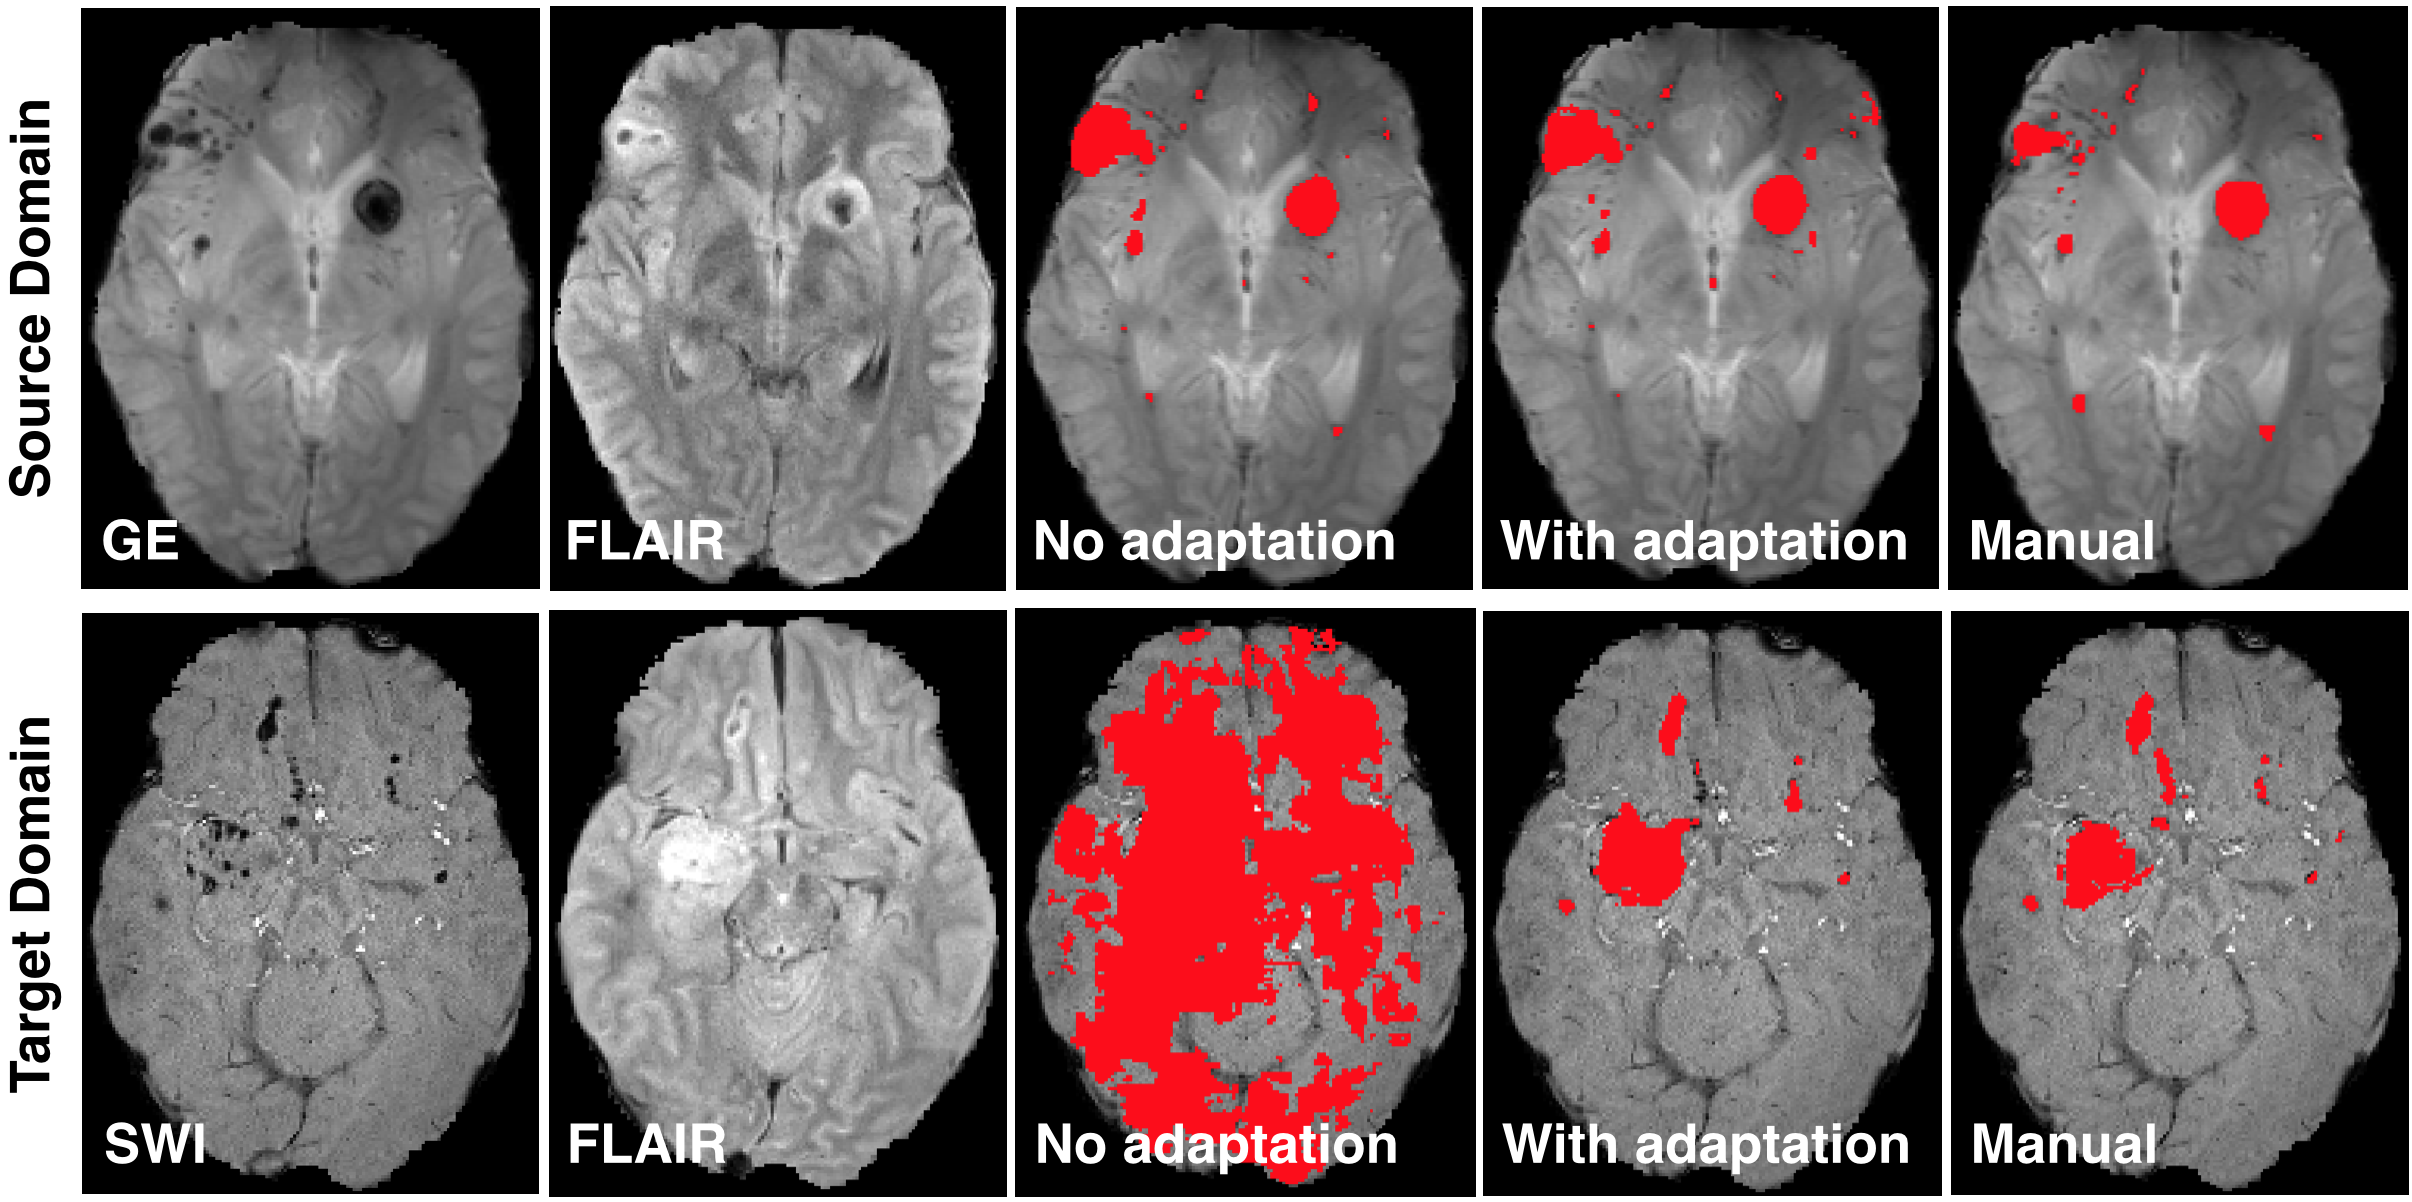

The theory and framework for domain adaptation via adversarial training presented in Sec. 4 has formed the basis for several works in biomedical image analysis. Kamnitsas et al. [52] proposed employing domain adversarial networks for alleviating problematic segmentation due to domain shift between MR acquisition protocols. Extending the basic framework, they proposed multi-connected adversarial nets, which enable the domain discriminator to process information from several layers of the feature extractor (Fig. 10). Empirical analysis showed that this leads to a higher quality domain classifier, hence flow of better gradients to the primary network and improved adaptation. By applying the technique to adapt between two databases of multi-modal MR brain scans with traumatic brain lesions, where one of the modalities differed (Fig. 11), they showed that domain adversarial training is applicable to 3D CNNs for volumetric image processing. This was previously questioned in the literature [53] due to memory constraints.

Refer to caption

Figure 11: Result from Kamnitsas et al [52]. A CNN for segmentation of brain lesions is trained on a database of multi-modal MR scans, which include gradient echo (GE) sequence. The CNN fails when it is applied on another study, where susceptibility weighted imaging was acquired instead of GE. Domain adaptation alleviates the issue.